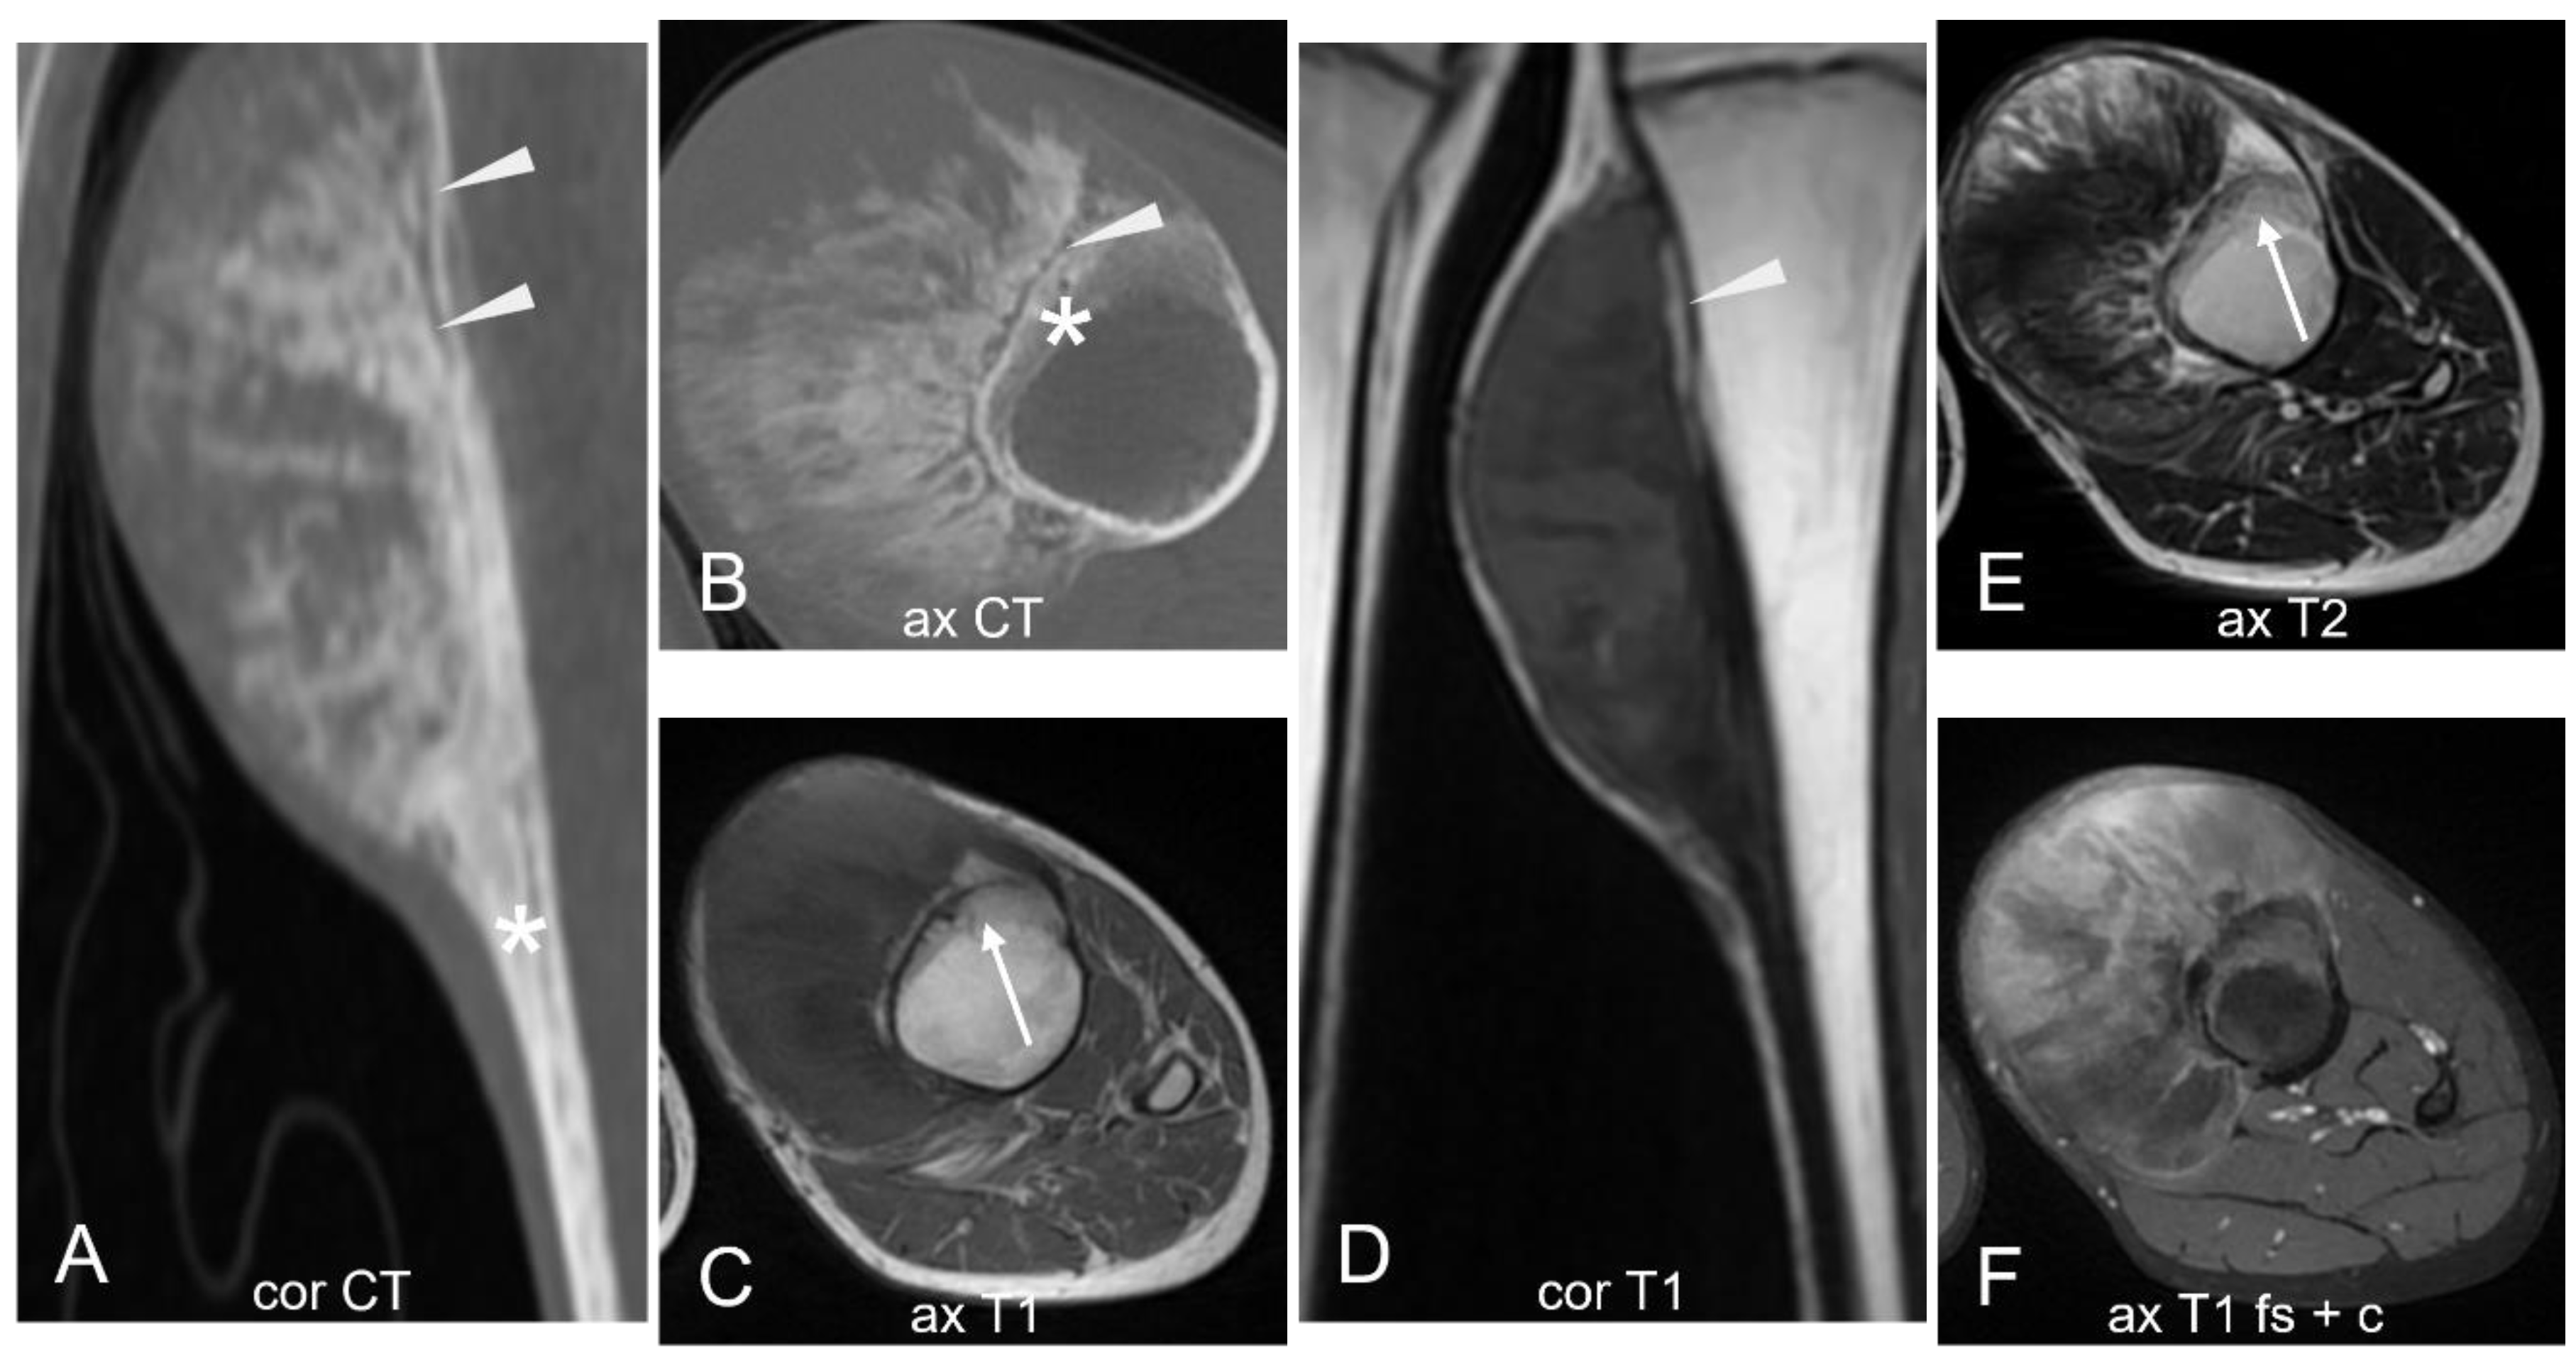

3.1.5. Low-Grade Central Osteosarcoma

- Malhas, A.M.; Sumathi, V.P.; James, S.L.; Menna, C.; Carter, S.R.; Tillman, R.M.; Jeys, L.; Grimer, R.J. Low-Grade Central Osteosarcoma: A Difficult Condition to Diagnose. Sarcoma 2012, 2012, 764796. [Google Scholar] [CrossRef]

- Andresen, K.J.; Sundaram, M.; Unni, K.K.; Sim, F.H. Imaging Features of Low-Grade Central Osteosarcoma of the Long Bones and Pelvis. Skeletal Radiol. 2004, 33, 373–379. [Google Scholar] [CrossRef] [PubMed]

- Choong, P.F.M.; Pritchard, D.J.; Rock, M.G.; Sim, F.H.; McLeod, R.A.; Unni, K.K. Low Grade Central Osteogenic Sarcoma A Long-Term Followup of 20 Patients. Clin. Orthop. Relat. Res. 1996, 322, 198. [Google Scholar] [CrossRef]

- Kurt, A.-M.; Unni, K.K.; McLeod, R.A.; Pritchard, D.J. Low-Grade Intraosseous Osteosarcoma. Cancer 1990, 65, 1418–1428. [Google Scholar] [CrossRef] [PubMed]